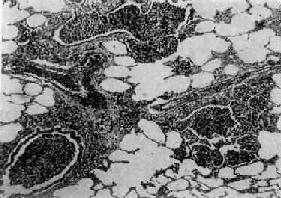

图9-14 左肺下叶大泡性肺气肿

在全腺泡型肺气肿基础上,胖有直径超过1cm的大囊泡